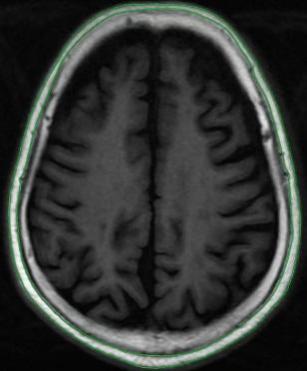

磁共振轴位SE T1WI图像及头皮下脂肪区域勾画示意图

Fig. 3

Magnetic resonance axial SE T1WI image and a schematic diagram outlining the subcutaneous fat area